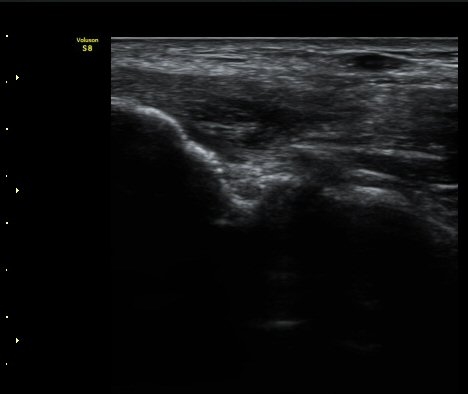

¼¶À¯ ¾ç»óÀ¸·Î °üÂûµÈ´Ù(±×¸² 4). ÈûÁ٠Ⱦ´Ü¸é °Ë»ç¿¡¼­µµ °Ç³» ¿¬°á¼º ¼Ò½Ç°ú Àú¿¡ÄÚ

º¯È­°¡ °üÂûµÈ´Ù(±×¸² 5).  ÃÊÀ½ÆÄÀ¯µµÇÏ ÁÖ»ç ½Ã ÁÖ»ç¾×ÀÌ °Ç³»¿¡¼­ ÀÚÀ¯·Ó°Ô ÆÛÁ®¼­

°ÇÀÇ ½ÉÇÑ ÆÄ¿­À» º¸¿©ÁØ´Ù(÷ºÎ ÆÄÀÏ µ¿¿µ»ó 1).